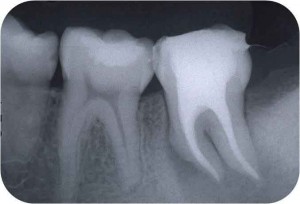

そこそこ細くて弯曲している根管より遙かに難しいのが、写真のような「太くて弯曲している根管」なのです。